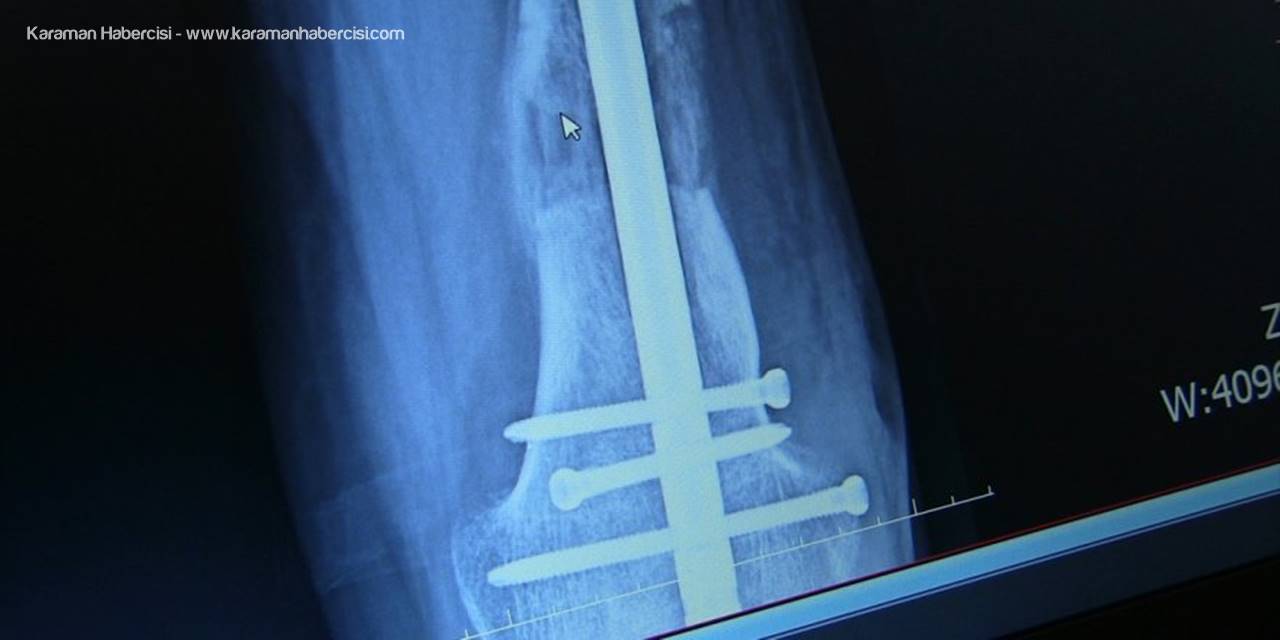

- Platin ve çivilerle ayağındaki kısalık giderildi

Hastanın yaşı ilerledikçe yürüme probleminin arttığını, sol ayağının sadece ayak parmaklarını yere basabildiğini dile getiren Arazi, "Hastamızın, ardışık ameliyatlarla bacağındaki kemikleri uzatabilme, dizindeki ve ayağındaki problemleri giderme kararı aldık. Yaptığımız ameliyatla ilk olarak bacağındaki şekil bozukluğunu düzelttik. Ardından tıbbi olarak kullandığımız çivi ve platinlerle dizin üstündeki ve dizin altındaki kemiği uzattık. Ardından topuk ve ayak bileğindeki bozukluk için de bir operasyon yaptık. Şu anda sağlığı iyi durumda." diye konuştu.